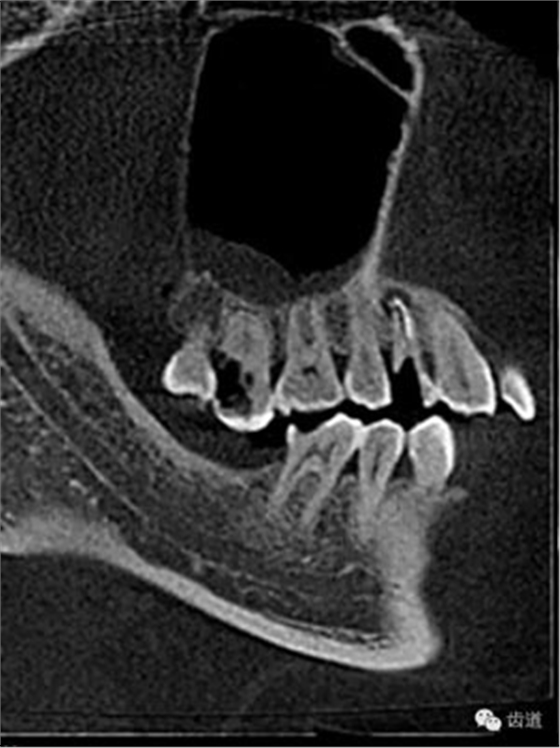

處理:1.建議CBCT檢查。

好的開始就是成功的一半。通過CBCT了解根管的位置,形態(tài),方向。

檢查顯示:近頰及腭根充填恰填,遠頰根管內(nèi)有少許充填物影像。根尖明顯低密度影像。